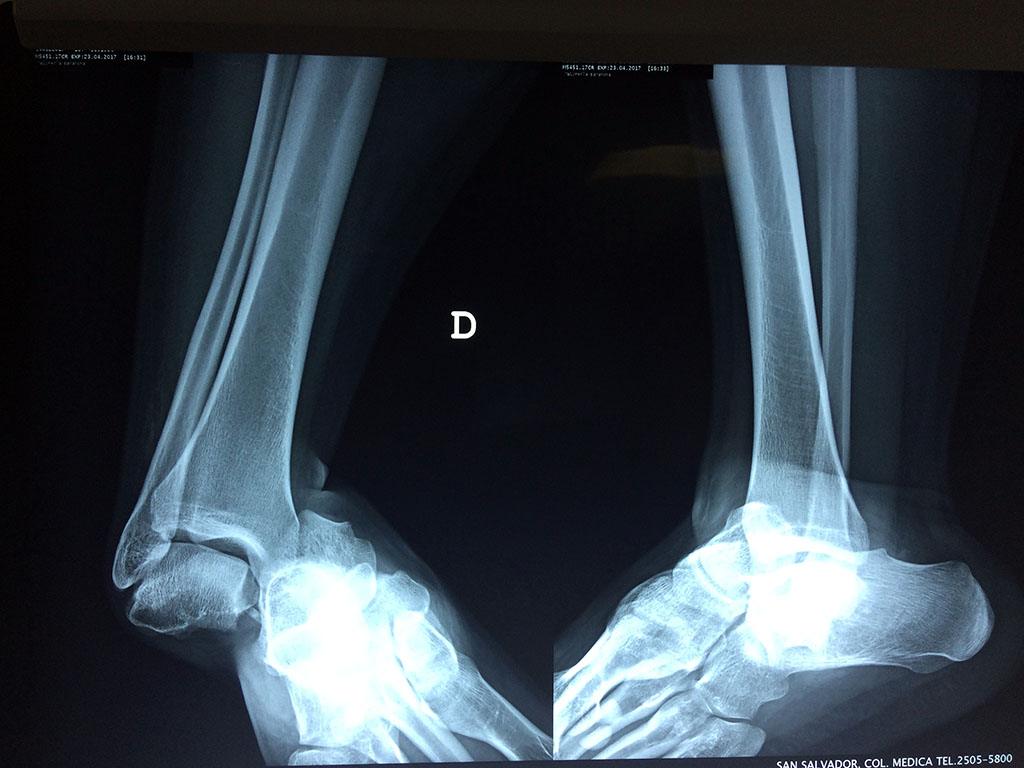

Una fractura de tobillo es la rotura de uno o más de los huesos del tobillo. Estas fracturas pueden ser:

- Parciales (el hueso está sólo parcialmente fisurado, no del todo).

- Completas (el hueso está perforado y está en 2 partes).

- Los extremos de los huesos están desalineados entre sí (desplazados).